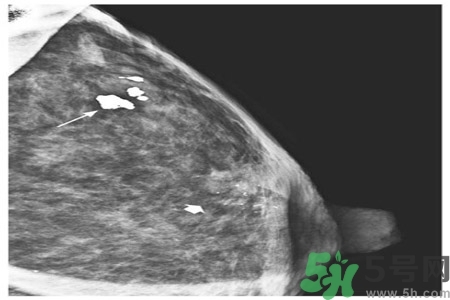

乳腺鈣化點(diǎn)是指可以在乳房造影片上看到鈣沉積物。乳房鈣化點(diǎn)有兩種類(lèi)型:大鈣化作用和微鈣化作用。

大鈣化作用通常是乳房?jī)?nèi)部的退行性改變,形成原因多是由于曾經(jīng)有損傷、發(fā)炎,或乳房動(dòng)脈的老化,并且通常與癌癥無(wú)關(guān)。

微鈣化作用是可能在迅速分解細(xì)胞的部位找到的鈣斑點(diǎn)。這些由迅速分解細(xì)胞留下的殘余物可以顯示為微鈣化作用。當(dāng)它們成群大量出現(xiàn)時(shí),即表示有小腫瘤的可能。

乳腺鈣化是指可以在乳房造影看到鈣沉淀物,有多種因素可導(dǎo)致乳腺鈣化,如組織退變、壞死鈣鹽沉積,某些腫瘤分泌含鈣鹽的物質(zhì),使血管周?chē)M織鈣化。分析鈣化的形態(tài)、數(shù)目、部位以及與周?chē)Y(jié)構(gòu)的關(guān)系,對(duì)辨別病變的性質(zhì)有較大的幫助。